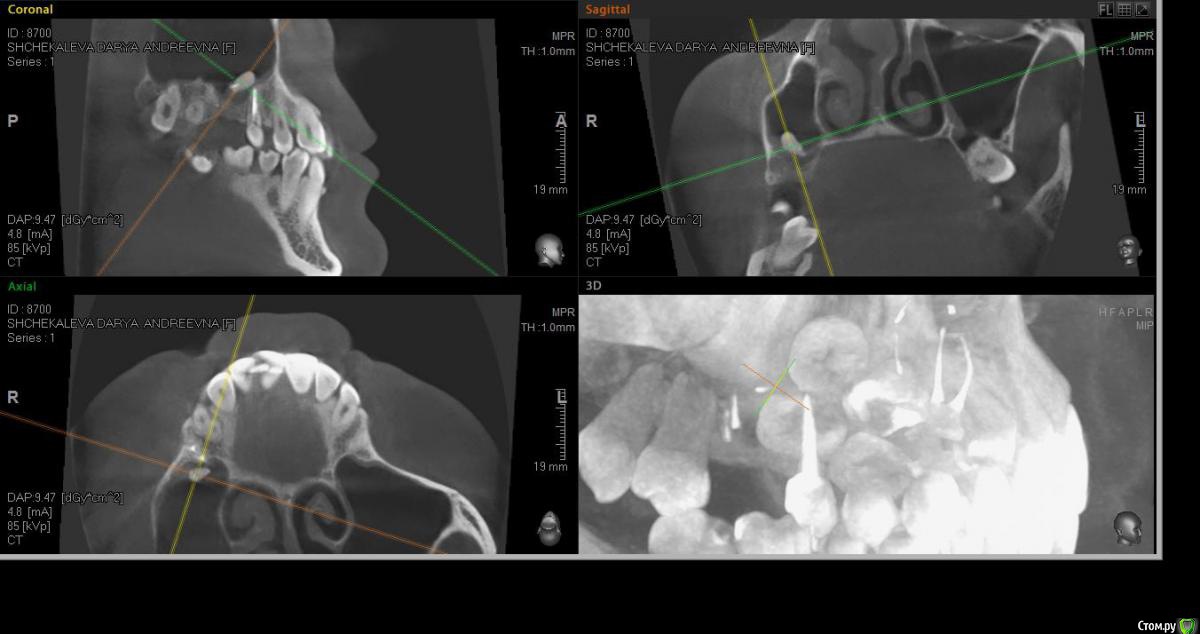

alekszander Опубликовано 14 марта, 2016 Поделиться Опубликовано 14 марта, 2016 Собственно вопрос кто сам доставал какие особенности? Или все же лучше к ЛОРу через эндоскоп?Боюсь только что корень с мембраной создал спайку и во время удаления просто порву мембрану.Дальние корни попробую аккуратно периотомом убрать. Ссылка на комментарий

faity Опубликовано 14 марта, 2016 Поделиться Опубликовано 14 марта, 2016 Можно со стороны альеолярки влезть, можно сразу окно выпилить.Для начала делаете доступ для визуализации, визуализируете апекс, потом аккуратно цепляете апикально чтобы мембрану не порвать, подойдёт кюретажка Лукаса маленькая 2мм и как с кистой или грануляцией вылущиваете. Если протолкнули- снимок и окно в проекции. 1 Ссылка на комментарий

alekszander Опубликовано 14 марта, 2016 Автор Поделиться Опубликовано 14 марта, 2016 Если протолкнули- снимок и окно в проекции.Что имеете ввиду если протолкнул, при попытке достать корень толкнул его глубже? И не совсем понял про снимок, помню читал тему, что его подшивают, но не совсем понял как в в данном случае - уложить и потом отдельно доставать? Ссылка на комментарий